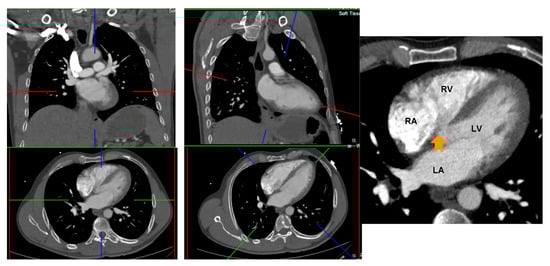

CT 2 and 4 chamber planes were created analogous to TTE views. Using multiplanar reformatting (MPR) with true axial stack, 2 and 4 chamber planes were created by positioning long axis reference line through LV apex and mid mitral valve, and short axis reference line parallel and aligned with mitral annular plane. Imaging slice height was adjusted cranio-caudally to remove LV outflow tract/aortic root from view, to avoid creation of TTE equivalent ‘5 chamber view’. The LV short axis plane was used for cross reference to ensure the manually created 2 and 4 chamber planes transected the appropriate and relevant myocardial segments; 2 chamber—anterior and inferior segments, 4 chamber—inferoseptum and anterolateral segment (Figure 2).

Figure 2.

Creation of 4 and 2 chamber planes on non-ECG-gated CTPA. Left panel: Source data prior to image manipulation. Middle panel: Alignment of crosshairs with long axis reference line through LV apex and mid mitral valve and short axis reference line parallel and aligned with mitral annular plane. Right panel: Avoid creation of a 5 chamber view by adjusting the image height (arrow points to left ventricular outflow tract). RA: right atrium; LA: left atrium; RV: right ventricle; LV: left ventricle.